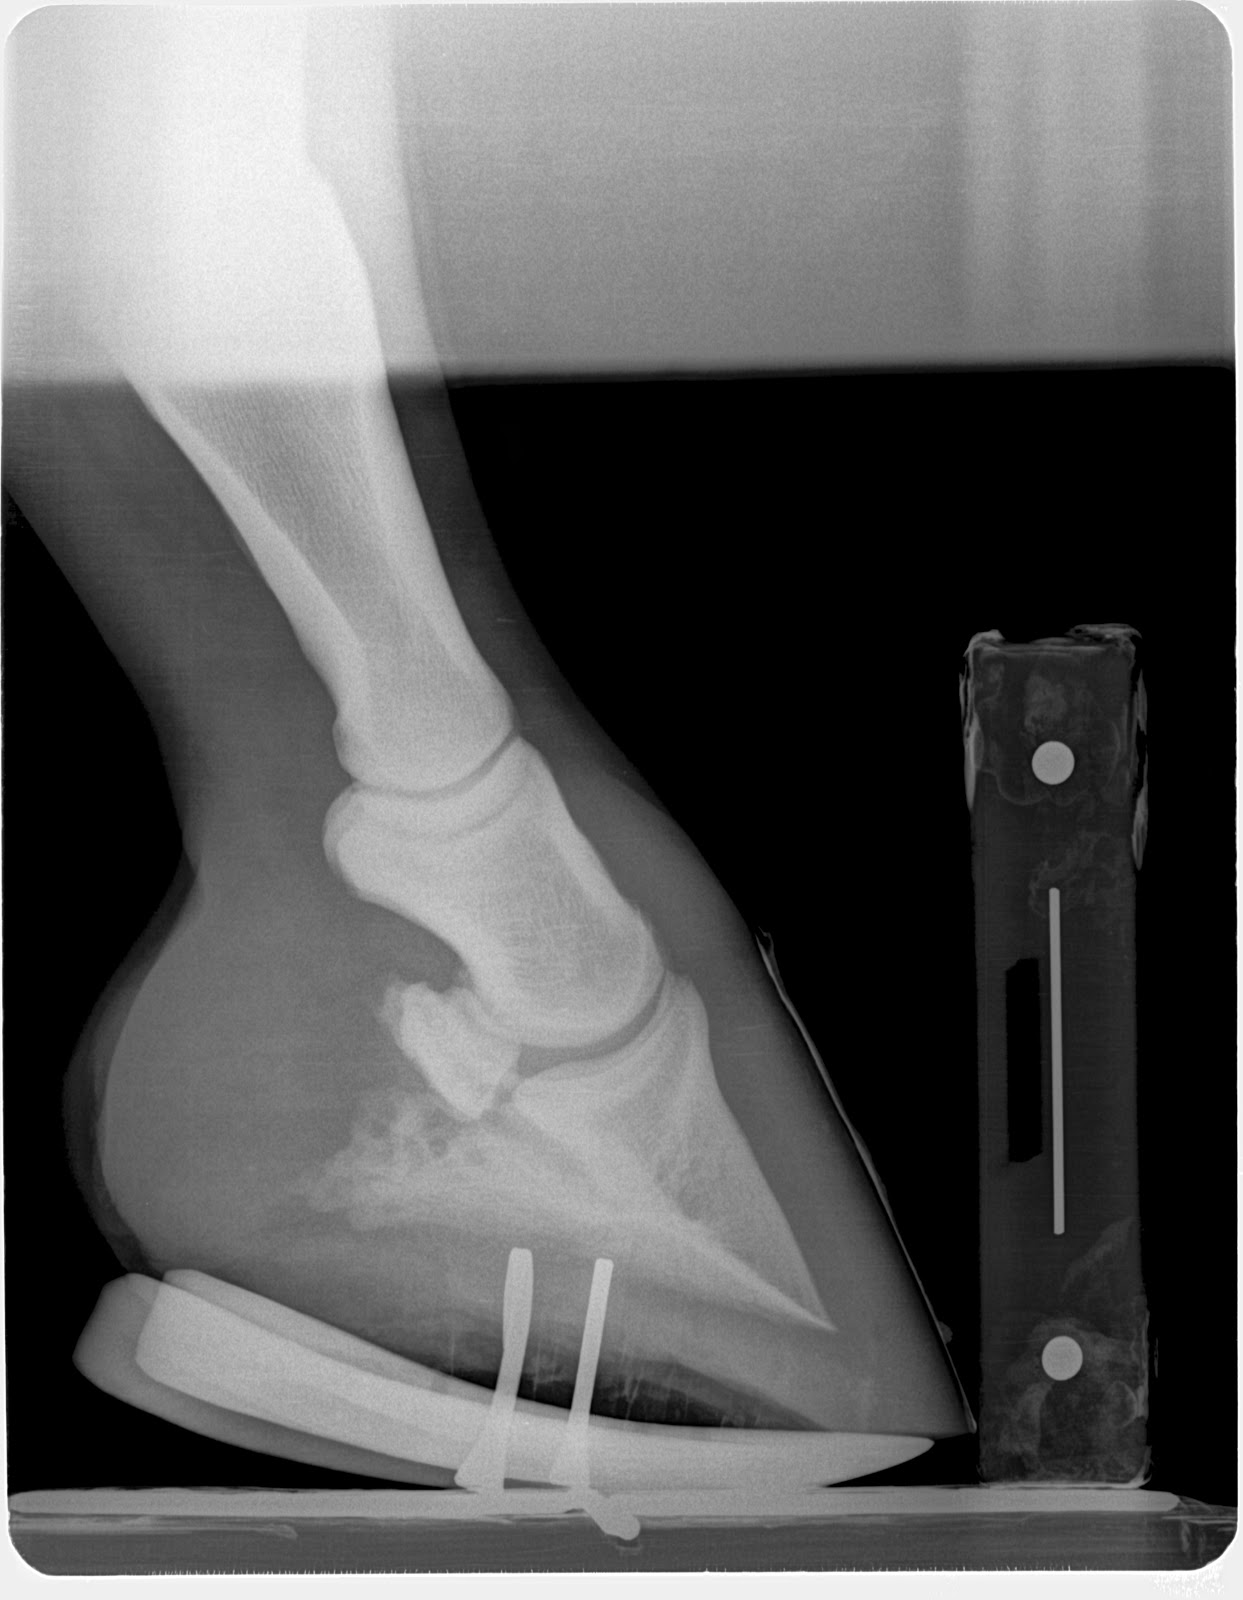

6 month chronic laminitis case: Owner reports horse is very comfortable, has a much better appetite and very willing to move freely. This case demonstrates the importance the deep digital flexor tendon force applied to a failed lamellar bone. With the loss of the lamellar suspension of the coffin bone, it is allowed to compress the sole at the apex of coffin. No blood, No growth and recurrent abscessation as has occurred in this case. The fragile rim of the coffin bone becomes loses its blood supply and acts like a foreign body. I haven't been able to achieve this level of success with any other approach. Doubling sole depth from 10mm to 20 mm in a matter of 6 wks in chronic laminitis is astonishing.

I do not recommend a tenotomy for every laminitis case and only do so if the venogram shows the circumflex artery at or above the level of the tip of the coffin bone as described by Dr. Ric Redden. However I do recommend considering the forces applied by the ddft to the coffin bone and often use "mechanics" (rockering/wedging) to lesson the tension on a failing system to aid in re-establishing vascular supply.

| Immediately post derotation and deep flexor tenotomy oct 6 |

| Note the rapid growth of sole at dorsal portion of hoof and loss of palmar angle. addition of 10mm of sole |

| Post reset to re establish a zero palmar angle with the shoe. This is necessary to prevent over correction resulting in a negative palmar angle |

| Immediately post derotation and deep flexor tenotomy on oct 6 |

| 6wks post derotational shoeing and deep flexor tenotomy. No reset required as even sole growth is occuring and resetting the shoe does not add any benefits mechanically. |